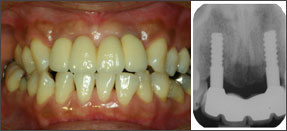

インプラントの場合、審美性を追求すると清掃性に問題が生じ、逆に清掃性を追求すると審美性は劣ってしまうという二律背反の要素の兼ね合いが重要である。そこで必要な清掃性を確保しつつ、その中でできるだけ審美性を追求することになる。1ピースの場合、2ピースほど冠のマージンが歯肉縁下深くないので口腔清掃上は有利であるが、セメント合着するので、歯肉縁下が深すぎると、余剰セメントの完全除去が困難となり、余剰セメントの残留が原因で慢性インプラント周囲炎を起こし、骨吸収を招くことがあるので注意が必要である。そのためには冠装着後のデンタルX線写真でセメント取り残しのチェックと、6ヵ月後健診でもデンタルX線写真とポケット検査を行うことが重要であると思う。もし、骨吸収やポケットデプスが進み、プロービングで疑わしい場合はフラップを開けてセメント掻爬をやるくらいの勇気が必要と思う。インプラントの近遠心での骨変化はデンタルX線写真に反映するが、唇・口蓋側での初期の骨吸収はX線像に現れないので注意が必要である。私は合着に3Mビトレーマ(グラスアイオノマー系レジンセメント)を使用してきたが、昨年発売になった余剰セメントの一塊除去がし易いというセールスポイントの松風ハイボンドレジグラス(同系統)なども試用している。

| 1ピースAQBインプラントの課題 | ||

![]() ? 2000/09/01 左上5、左上6 連結MBCr装着時 |

![]() ? その2Y後にみられた残留セメントの褥瘡による頬側粘膜の穿孔(fenestration) |

![]() ? 2005/05/18 粘膜退縮により残留セメントは消失している |